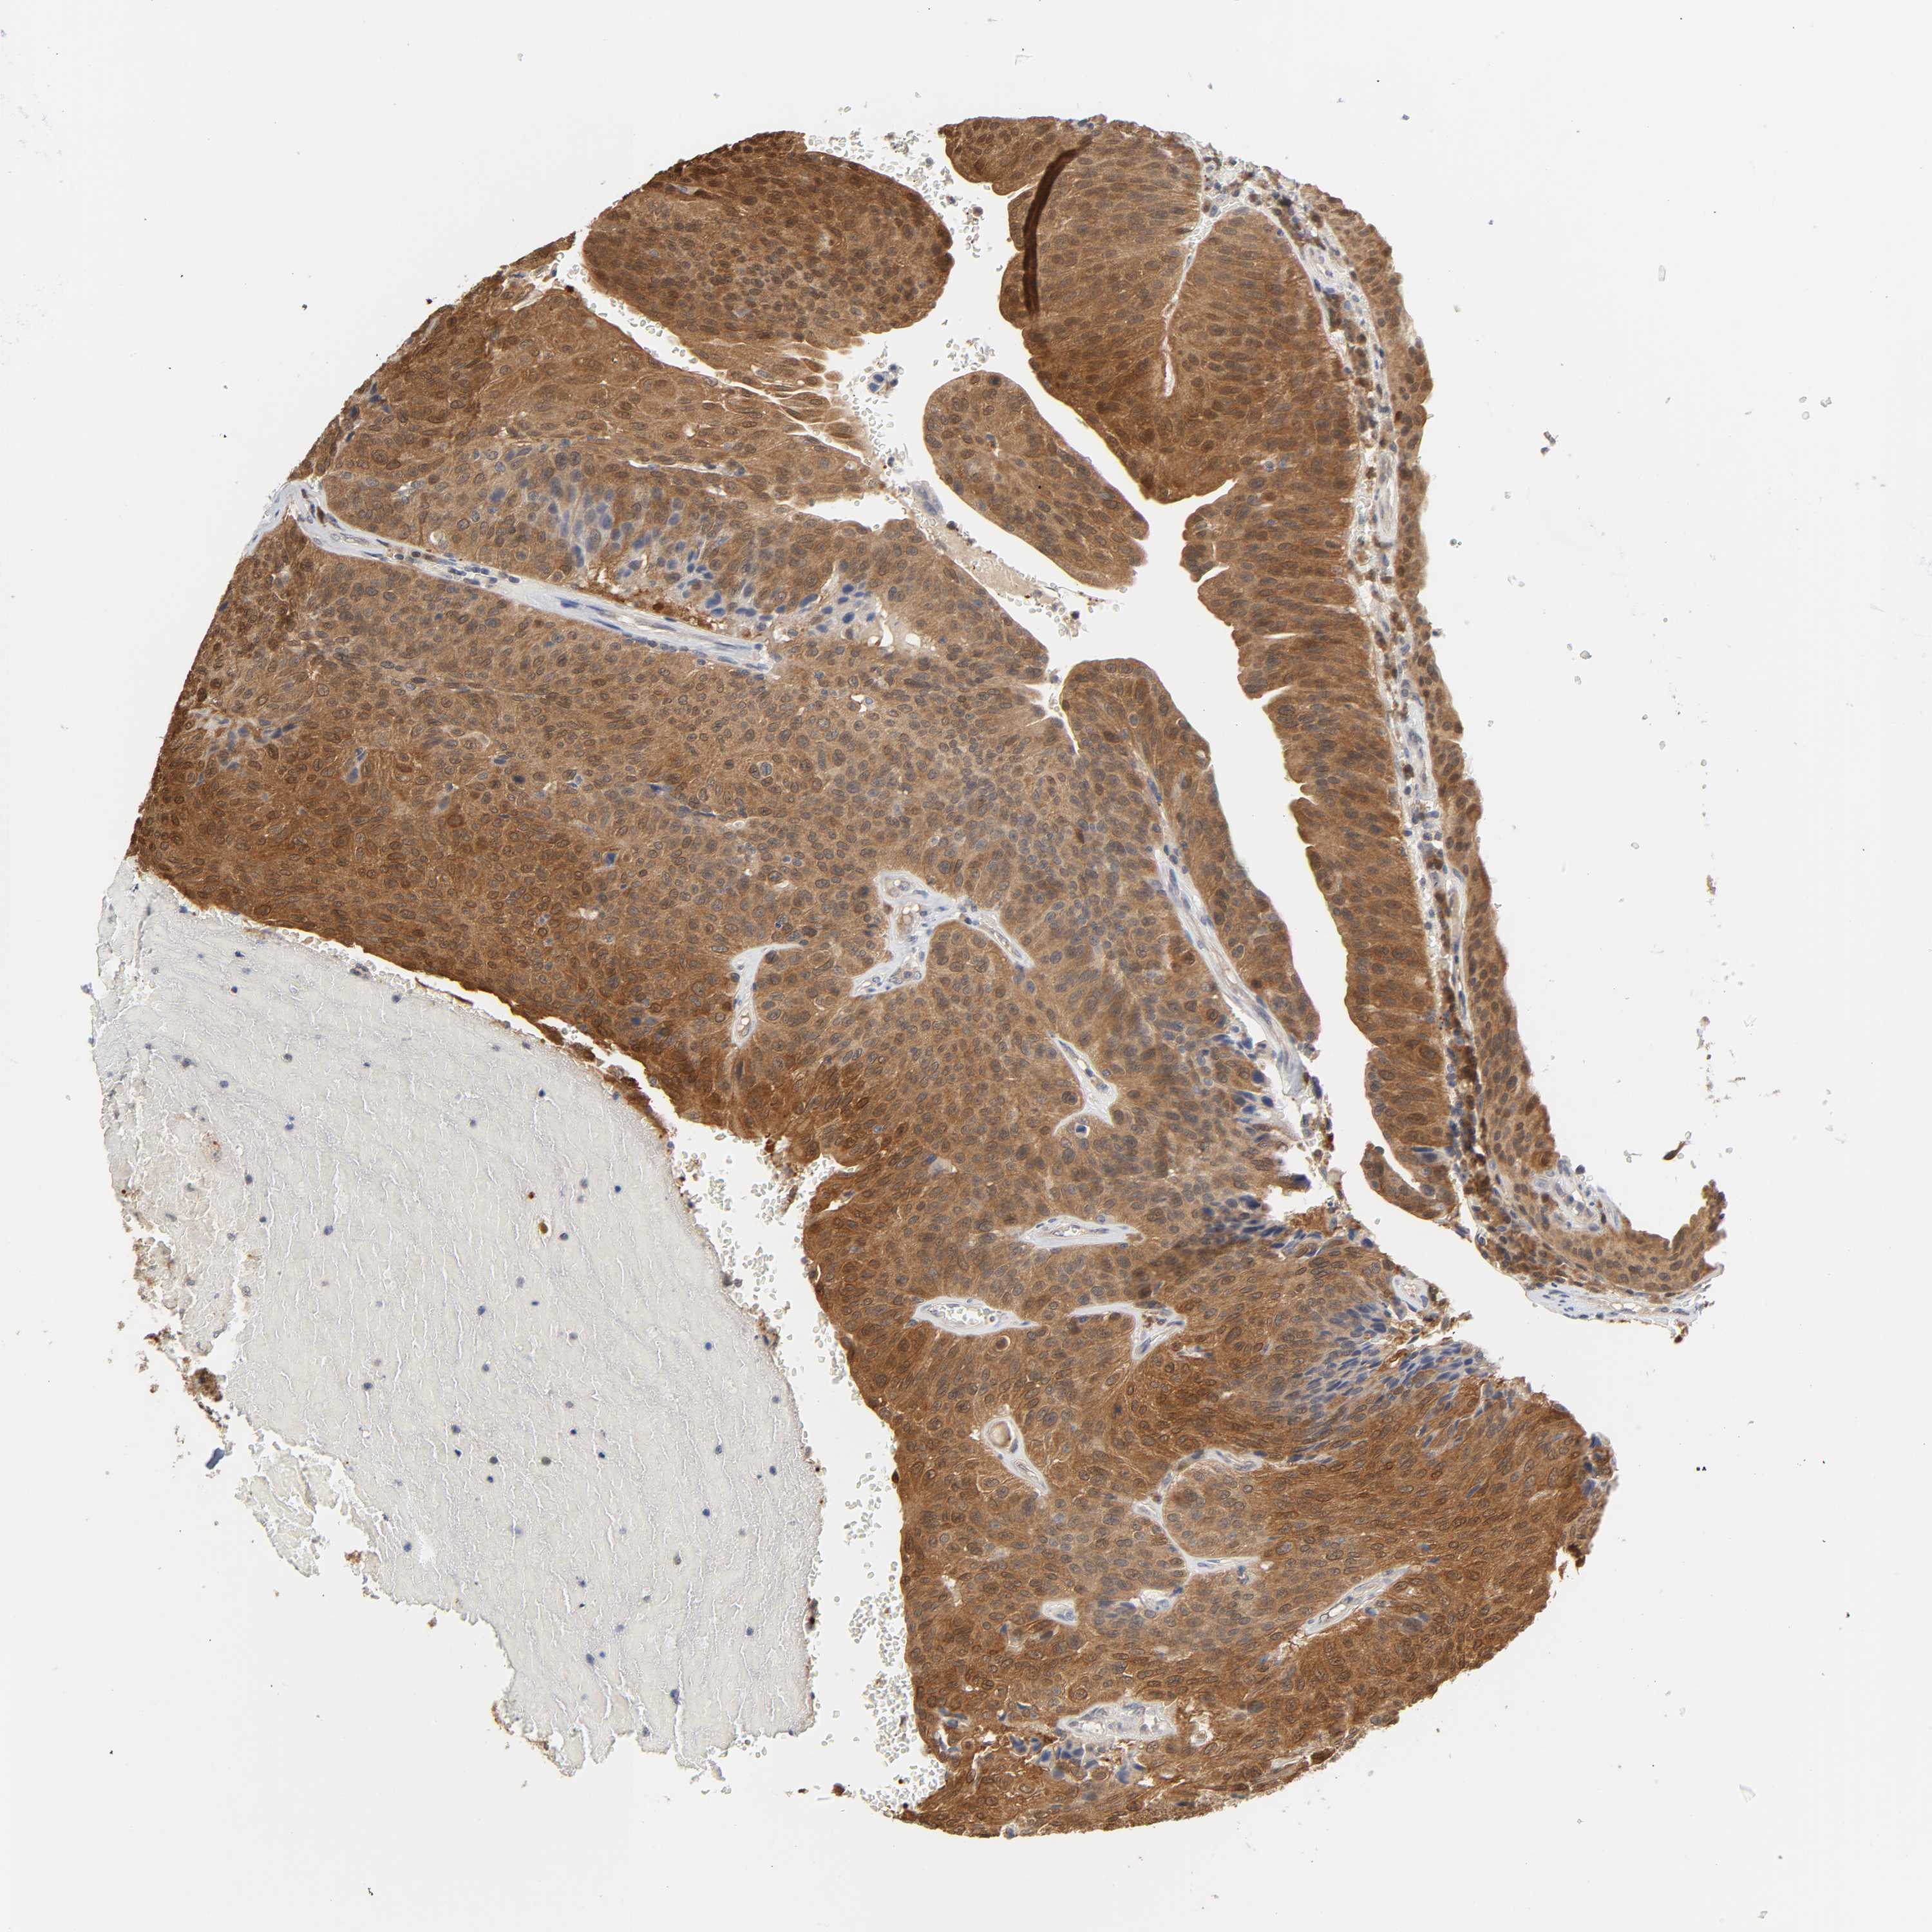

UROTHELIAL CANCER - Protein expressioni

A mouse-over function shows sample information and annotation data. Click on an image to view it in a full screen mode. Samples can be filtered based on level of antibody staining by selecting one or several of the following categories: high, medium, low and not detected. The assay and annotation is described here.

Note that samples used for immunohistochemistry by the Human Protein Atlas do not correspond to samples in the TCGA dataset.

Antibody stainingi

Antibody staining in the annotated cell types in the current human tissue is reported as not detected, low, medium, or high, based on conventional immunohistochemistry profiling in selected tissues. This score is based on the combination of the staining intensity and fraction of stained cells.

Each image is clickable and will lead to virtual microscopy that enables deeper exploration of all samples and also displays staining intensity scores, fraction scores and subcellular localization as well as patient and tissue information for each sample.

Antibody HPA003868

Antibody CAB005284

Staining

High

Medium

Low

Not detected

Intensity

Strong

Moderate

Weak

Negative

Quantity

>75%

75%-25%

<25%

None

Location

Nuclear

Cytoplasmic/membranous

Cytoplasmic/membranous,nuclear

Urothelial carcinoma, High grade

Urothelial carcinoma, Low grade